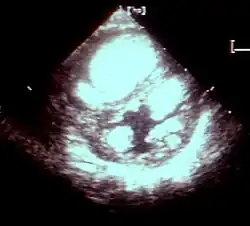

Rhabdomyome des Herzens kommen gehäuft bei der autosomal, dominant vererbten bzw. als Spontanmutation entstandenen tuberösen Sklerose vor. Sie treten ab etwa dem zweiten Schwangerschaftsdrittel (etwa ab der 20. Schwangerschaftswoche) auf, wachsen dann oft bis zur Geburt und schrumpfen danach, insbesondere in den ersten vier Lebensjahren, danach langsamer. Bis zum 20. Lebensjahr sind sie so gut wie immer verschwunden. Nach den bisherigen Erfahrungen treten neue Rhabdomyome spätestens nach dem Kleinkindesalter nicht mehr neu auf. Rhabdomyome des Herzens entstehen zu etwa 80 % im Rahmen einer tuberösen Sklerose (TSC), bei etwa 20 % der Betroffenen liegt keine TSC vor. Kinder mit TSC haben zu über 50 % Rhabdomyome.

Rhabdomyome machen weit überwiegend keine klinischen Beschwerden und haben eine gute klinische Prognose. Sie können allerdings Herzrhythmusstörungen verursachen, die aber bei der TSC auch ohne nachweisbare Rhabdomyome beobachtet wurden. Warum Rhabdomyome nach der Geburt schrumpfen, ist nicht bekannt. Todesfälle infolge kardialer Rhabdomyome sind extrem selten und betreffen nach bisherigen Erfahrungen anscheinend nur Neugeborene. Wenn Rhabdomyome des Herzens im Neugeborenen- oder Kindesalter keine Beschwerden machen, sind operative Maßnahmen so gut wie nie erforderlich. Anzahl und Größe von Rhabdomyomen lassen keine Rückschlüsse auf den Schweregrad anderer Organmanifestationen bei TSC zu.